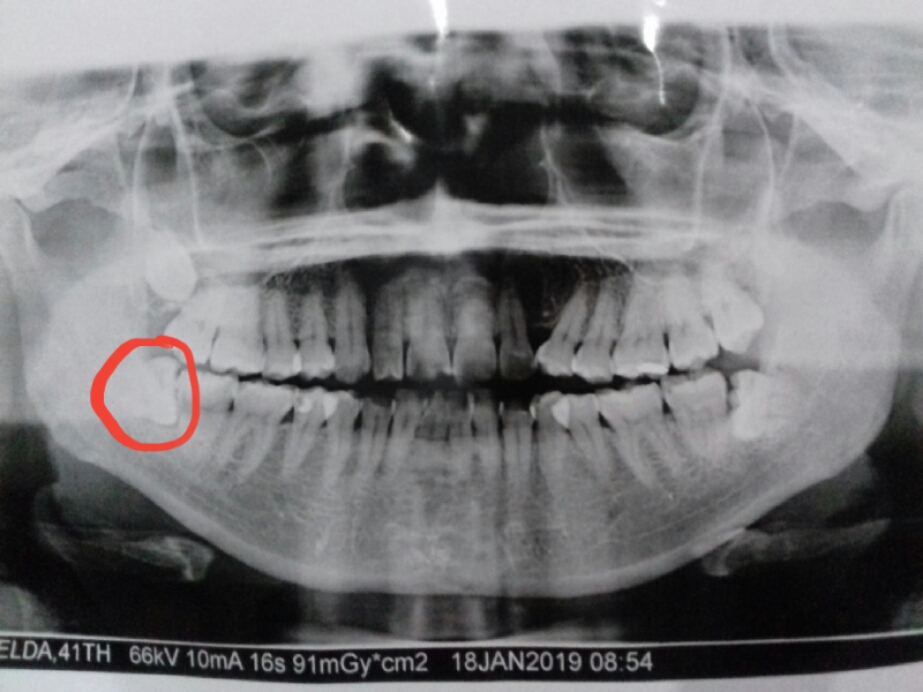

PREVALENSI AKAR GIGI MOLAR YANG MASUK RONGGA

PREVALENSI AKAR GIGI MOLAR YANG MASUK RONGGA